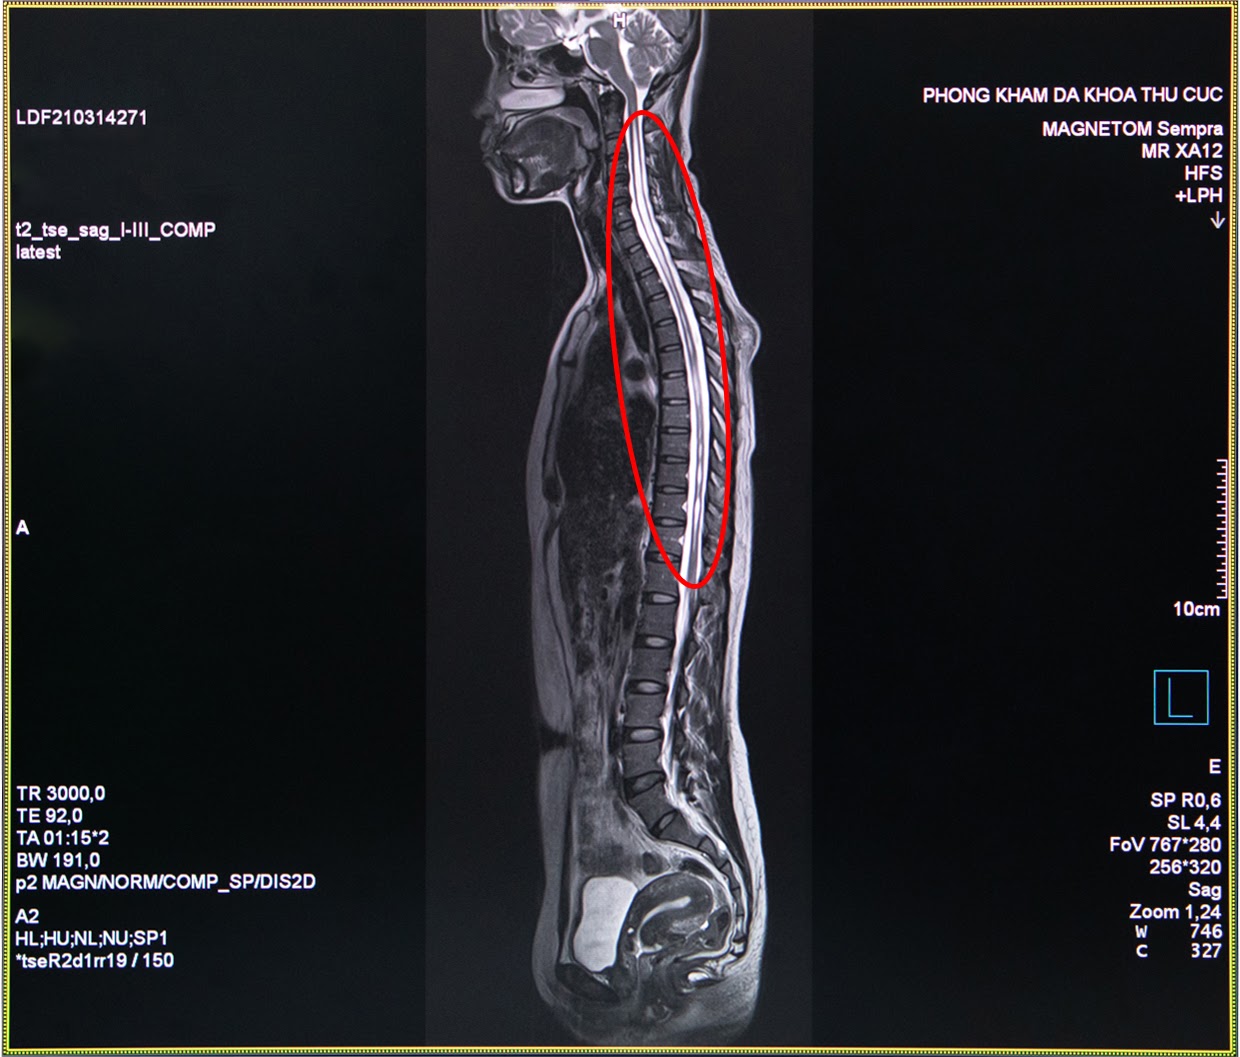

Chụp cộng hưởng từ MRI được xem là “tiêu chuẩn vàng” trong chẩn đoán nhiều bệnh về xương

Bác sĩ chẩn đoán hình ảnh Nguyễn Chí Phồn - Phòng khám đa khoa Thu Cúc cho biết: “Trường hợp của chị H. là chụp cộng hưởng tử MRI cột sống và tuỷ sống có tiêm thuốc đối quang từ nhằm phát hiện những tổn thương thần kinh. Đây là công cụ đáng tin cậy nhất để chẩn đoán bệnh rỗng tuỷ sống. Đối với những trường hợp nghi ngờ bệnh nhân bị rỗng tủy sống nếu chỉ định chụp X- Quang hay chụp cắt lớp vi tính MSCT sẽ khó có thể đánh giá chính xác được”.

Hình ảnh thu được từ chụp cộng hưởng từ MRI tủy sống của chị H. cho thấy trong đoạn tủy sống của chị hình thành một hốc rỗng chứa các dịch, các dịch này tích lại thành các khoang và nang hốc đây là biểu hiện của căn bệnh rỗng tủy. Ngay sau khi có kết quả khám cận lâm sàng, các bác sĩ của Thu Cúc đã hội chẩn nhằm xác định căn nguyên bệnh và tìm ra phương pháp điều trị tốt nhất cho chị H.